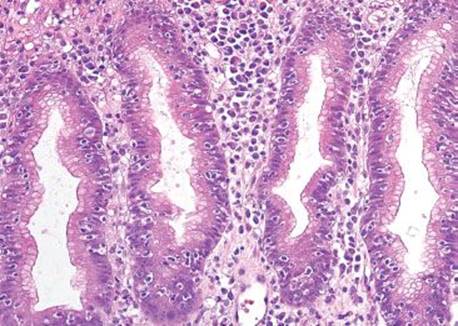

Figure 2.120 Lymphocytic gastritis pattern. This pattern of injury characteristically includes a mononuclear infiltrate in the lamina propria, but it differs from other types of chronic gastritis by the presence of increased intraepithelial lymphocytes (IELs), defined as >25 IELs per 100 epithelial cells.

Lymphocytic gastritis differs from chronic gastritis by the presence of increased intraepithelial lymphocytes (IELs), defined as more than 25 intraepithelial lymphocytes per 100 epithelial cells (Figs. 2.120–2.126).38,91–97 The term “lymphocytic gastritis” was originally used to describe the histologic counterpart to “varioliform” gastritis (i.e., thickened rugal folds and erosions), but subsequent studies have shown this association in only 3.9% to 30% of cases. More commonly, the endoscopic image shows erythema but up to 50% of patients have a normal endoscopic appearance. Although the etiology of the inflammation remains unknown in up to 20% of cases, common associations include infection (e.g., Helicobacter, HIV), celiac disease and other immune-mediated disorders (common variable immunodeficiency, Crohn disease, lymphocytic enterocolitis), medications, and neoplasia (Figs. 2.127–2.142).98 As a result, recognition of the lymphocytic gastritis pattern can serve as an important red flag to the underlying diagnosis and, consequently, lead to effective therapy with resolution of symptoms. The changes affect the entire stomach, but intraepithelial lymphocytes are most evident in the oxyntic mucosa, and are more prominent in the superficial epithelium than the glands. Most cases show expansion of the lamina propria with a mixed lymphoplasmacytic inflammatory infiltrate, in addition to the intraepithelial lymphocytosis (Fig. 2.121). Regenerative and hyperplastic changes in the surface epithelium may be present, analogous to the surface changes seen with intraepithelial lymphocytosis of the small and large bowel. Immunolabeling identifies these as CD3+ T cells, with about 80% showing a cytotoxic/suppressor CD8+ phenotype. Most patients respond to treatment of their associated condition, when a known etiology is present (i.e., successful eradication of Helicobacter usually leads to reduced symptoms and decreased inflammation in biopsies, and adherence to a gluten-free diet typically results in clinical and histologic improvement in patients with celiac disease). Others advocate empiric Helicobacter eradiation, even in Helicobacter-negative patients. In general, immunosuppressive medications are reserved for those who fail gluten withdrawal and whose intraepithelial lymphocytosis involves the stomach, small, and large bowel. Untreated lymphocytic gastritis may persist for years, although spontaneous remission has been reported.

Figure 2.121 Lymphocytic gastritis pattern. The changes of lymphocytic gastritis are often prominent enough that they can be identified at scanning magnification, obviating the need for intraepithelial lymphocyte counts. The IELs usually affect the entire stomach but are more evident in the oxyntic mucosa and are more prominent in the superficial epithelium as compared to the deeper glands. Note the diffuse mixed inflammatory infiltrate in the lamina propria.